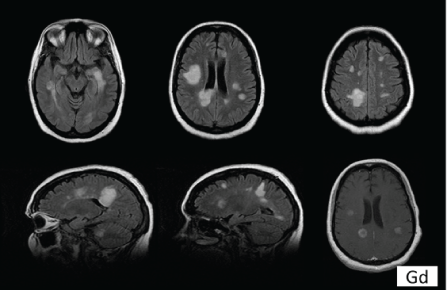

图1:脑MRI(FLAIR)显示几个高强度病变,符合巴克霍夫空间扩散标准:1)≥ 9个大小至少为3 mm的T2病变,或≥ 1钆增强病变,2)≥ 3例脑室周围病变,3例)≥ 1个皮质旁病变和4个)≥ 1幕下病变。

一名46岁妇女因吞咽困难问题被转到神经内科。异常的脑MRI显示多个T2和FLAIR高强度/病变,符合Barkhof的四种空间播散标准中的三种(图1)。她有人格障碍,曾因痉挛性发音障碍在Othorhinolaringology服务中接受治疗。经过特别询问,她从未表现出脱髓鞘疾病的临床征兆。在对她的精神障碍进行治疗后,吞咽困难得到改善。我们决定在6个月后进行对照MRI检查,未发现新的病变。咨询10个月后,患者因人格障碍恶化、家庭动态恶化、冲动控制减少和行为退化而被送入精神健康服务中心。神经系统检查显示她精神状态改变,左侧面神经麻痹,左侧肢体感觉减退,步态不稳定。扩展残疾状态量表(EDSS)得分为6分。此时,进行了新的脑部MRI检查,发现多个肿块,钆增强(图2)。颈脊髓MRI正常。视觉诱发电位(VEP)显示双侧脱髓鞘视神经病变,脑脊液(CSF)中可见IgG寡克隆条带。 The patient was put on treatment with natalizumab. After 6 months of this treatment, her state of health had improved (EDDS score of 3) and a new MRI showed a reduction in the size of the lesions, which were not enhanced with gadolinium.